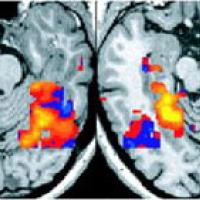

A functional MRI scan of a person's brain.